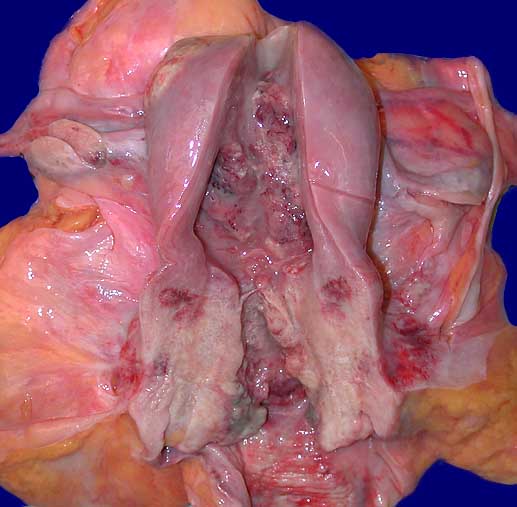

PathoPic – image database / PathoPic ID 6764 - Zervixkarzinom und Endometriumkarzinom

Zervixkarzinom und Endometriumkarzinom

Längsschnitt durch den Uterus. Die Zervix ist aufgetrieben durch einen gelblich-weissen Tumor. Exophytischer Tumor im Bereich des Uteruscavum mit Infiltration bis unter die Serosa. Angeschnittenes tumorfreies Ovar.

Histologie: endometrioides Karzinom des Cavums und Plattenepithelkarzinom der Zervix.